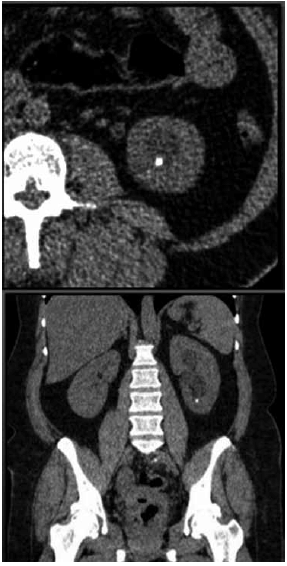

Mulher de 48 anos apresenta quadro de dor recorrente em região lombar à esquerda. Realizado tomografia de abdome total sem contraste (imagem demonstrada), que evidenciou cálculo em cálice inferior de 0,7 cm (400 UH). A análise da via de saída do cálice inferior demonstrou: ângulo infundíbulo-pielico de 95 graus e infundíbulo com comprimento de 1,0 cm.